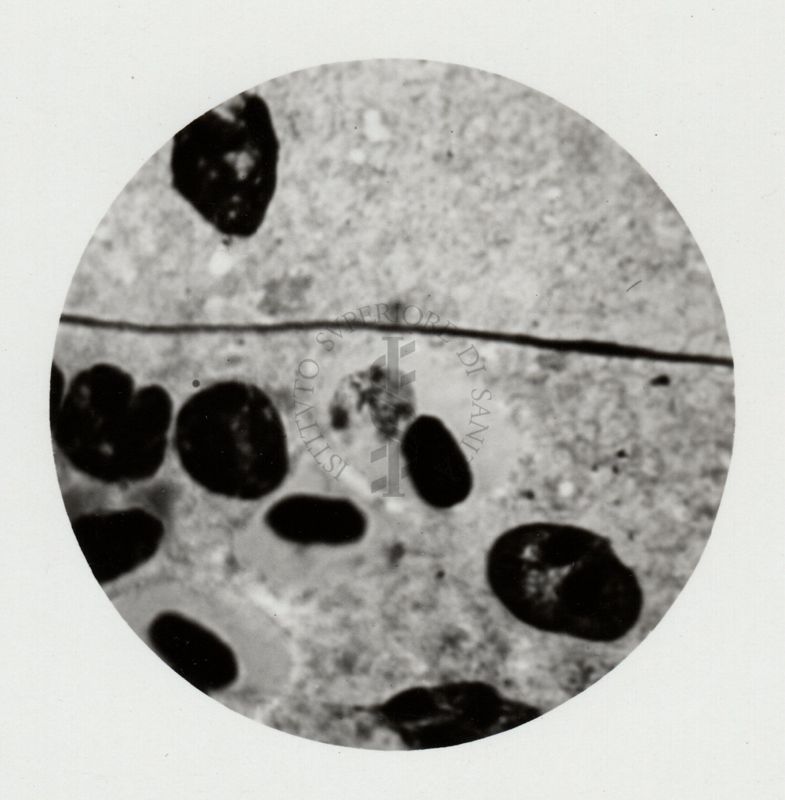

Milza di canarino

Roma, 18 dicembre 1939 - 27 gennaio 1940

PAR.00125B,00126B e 00129B